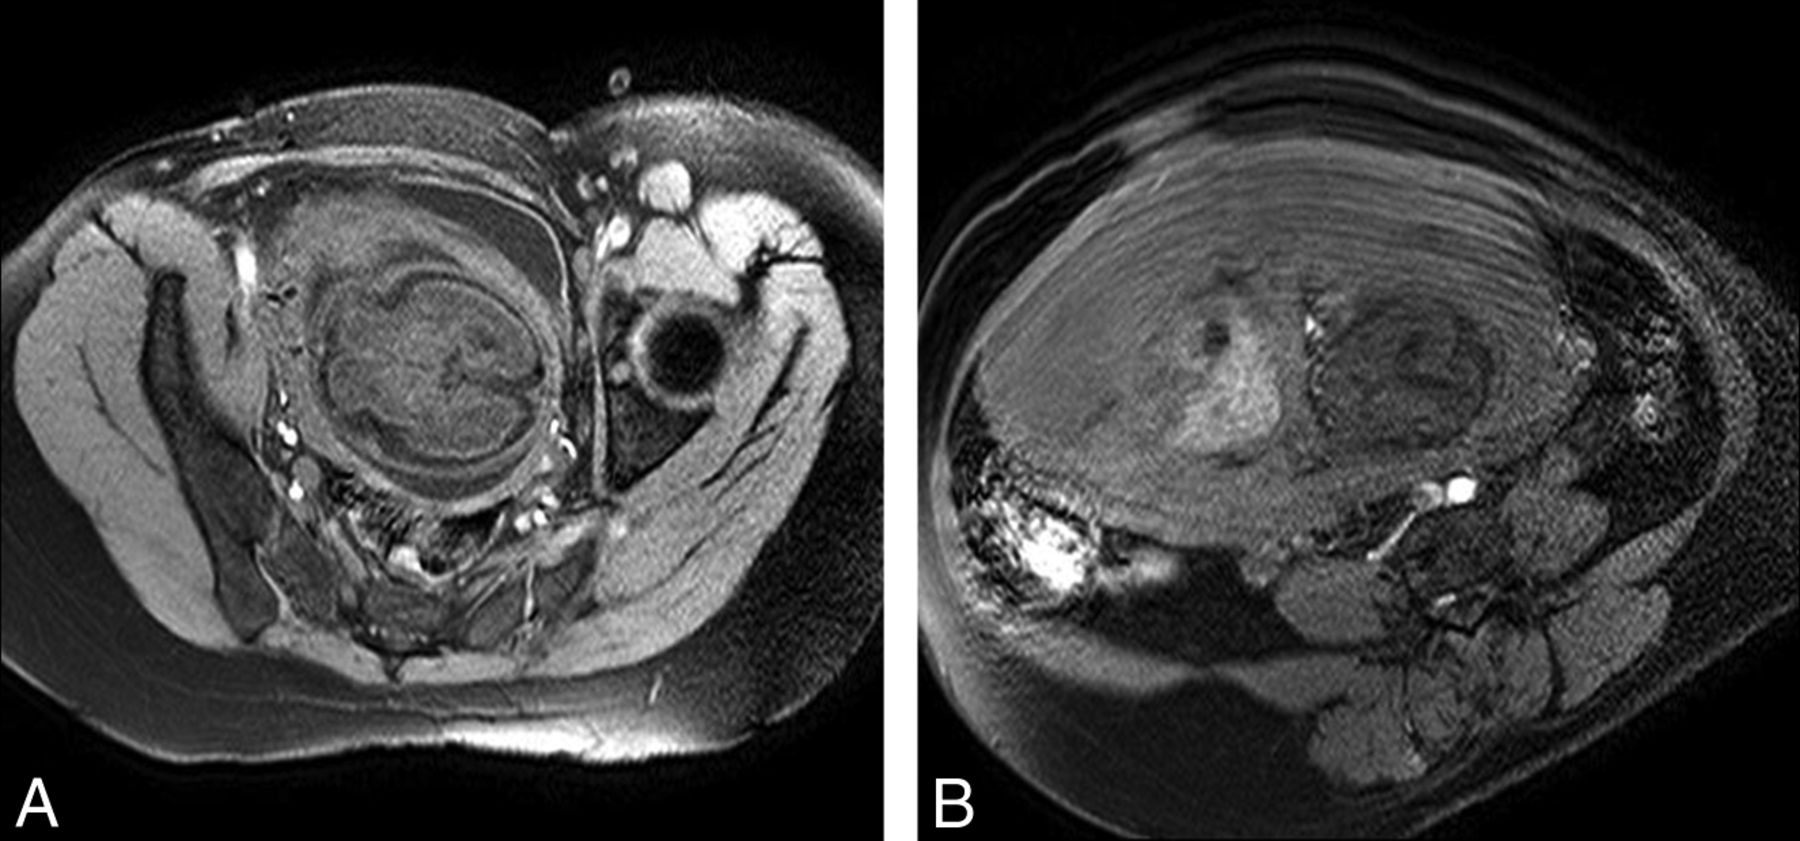

Successive axially planned sections of a single-shot fast-spin-echo acquisition at 1.5T (TR, 1000 ms; TE, 127 ms; section thickness, 4 mm; scanning duration, 26 seconds) of a 32-week-old fetus (E) with significant fetal motion occurring during data acquisition and resulting in blurring (C, J, M), contrast changes (P), and ultimately signal void when motion is extreme (B). Please note that though sections were planned in the axial plane, fetal movement resulted in plane transposition in the produced images (A–P) (fetal brain is circumscribed in red to distinguish it from neighboring maternal tissues).